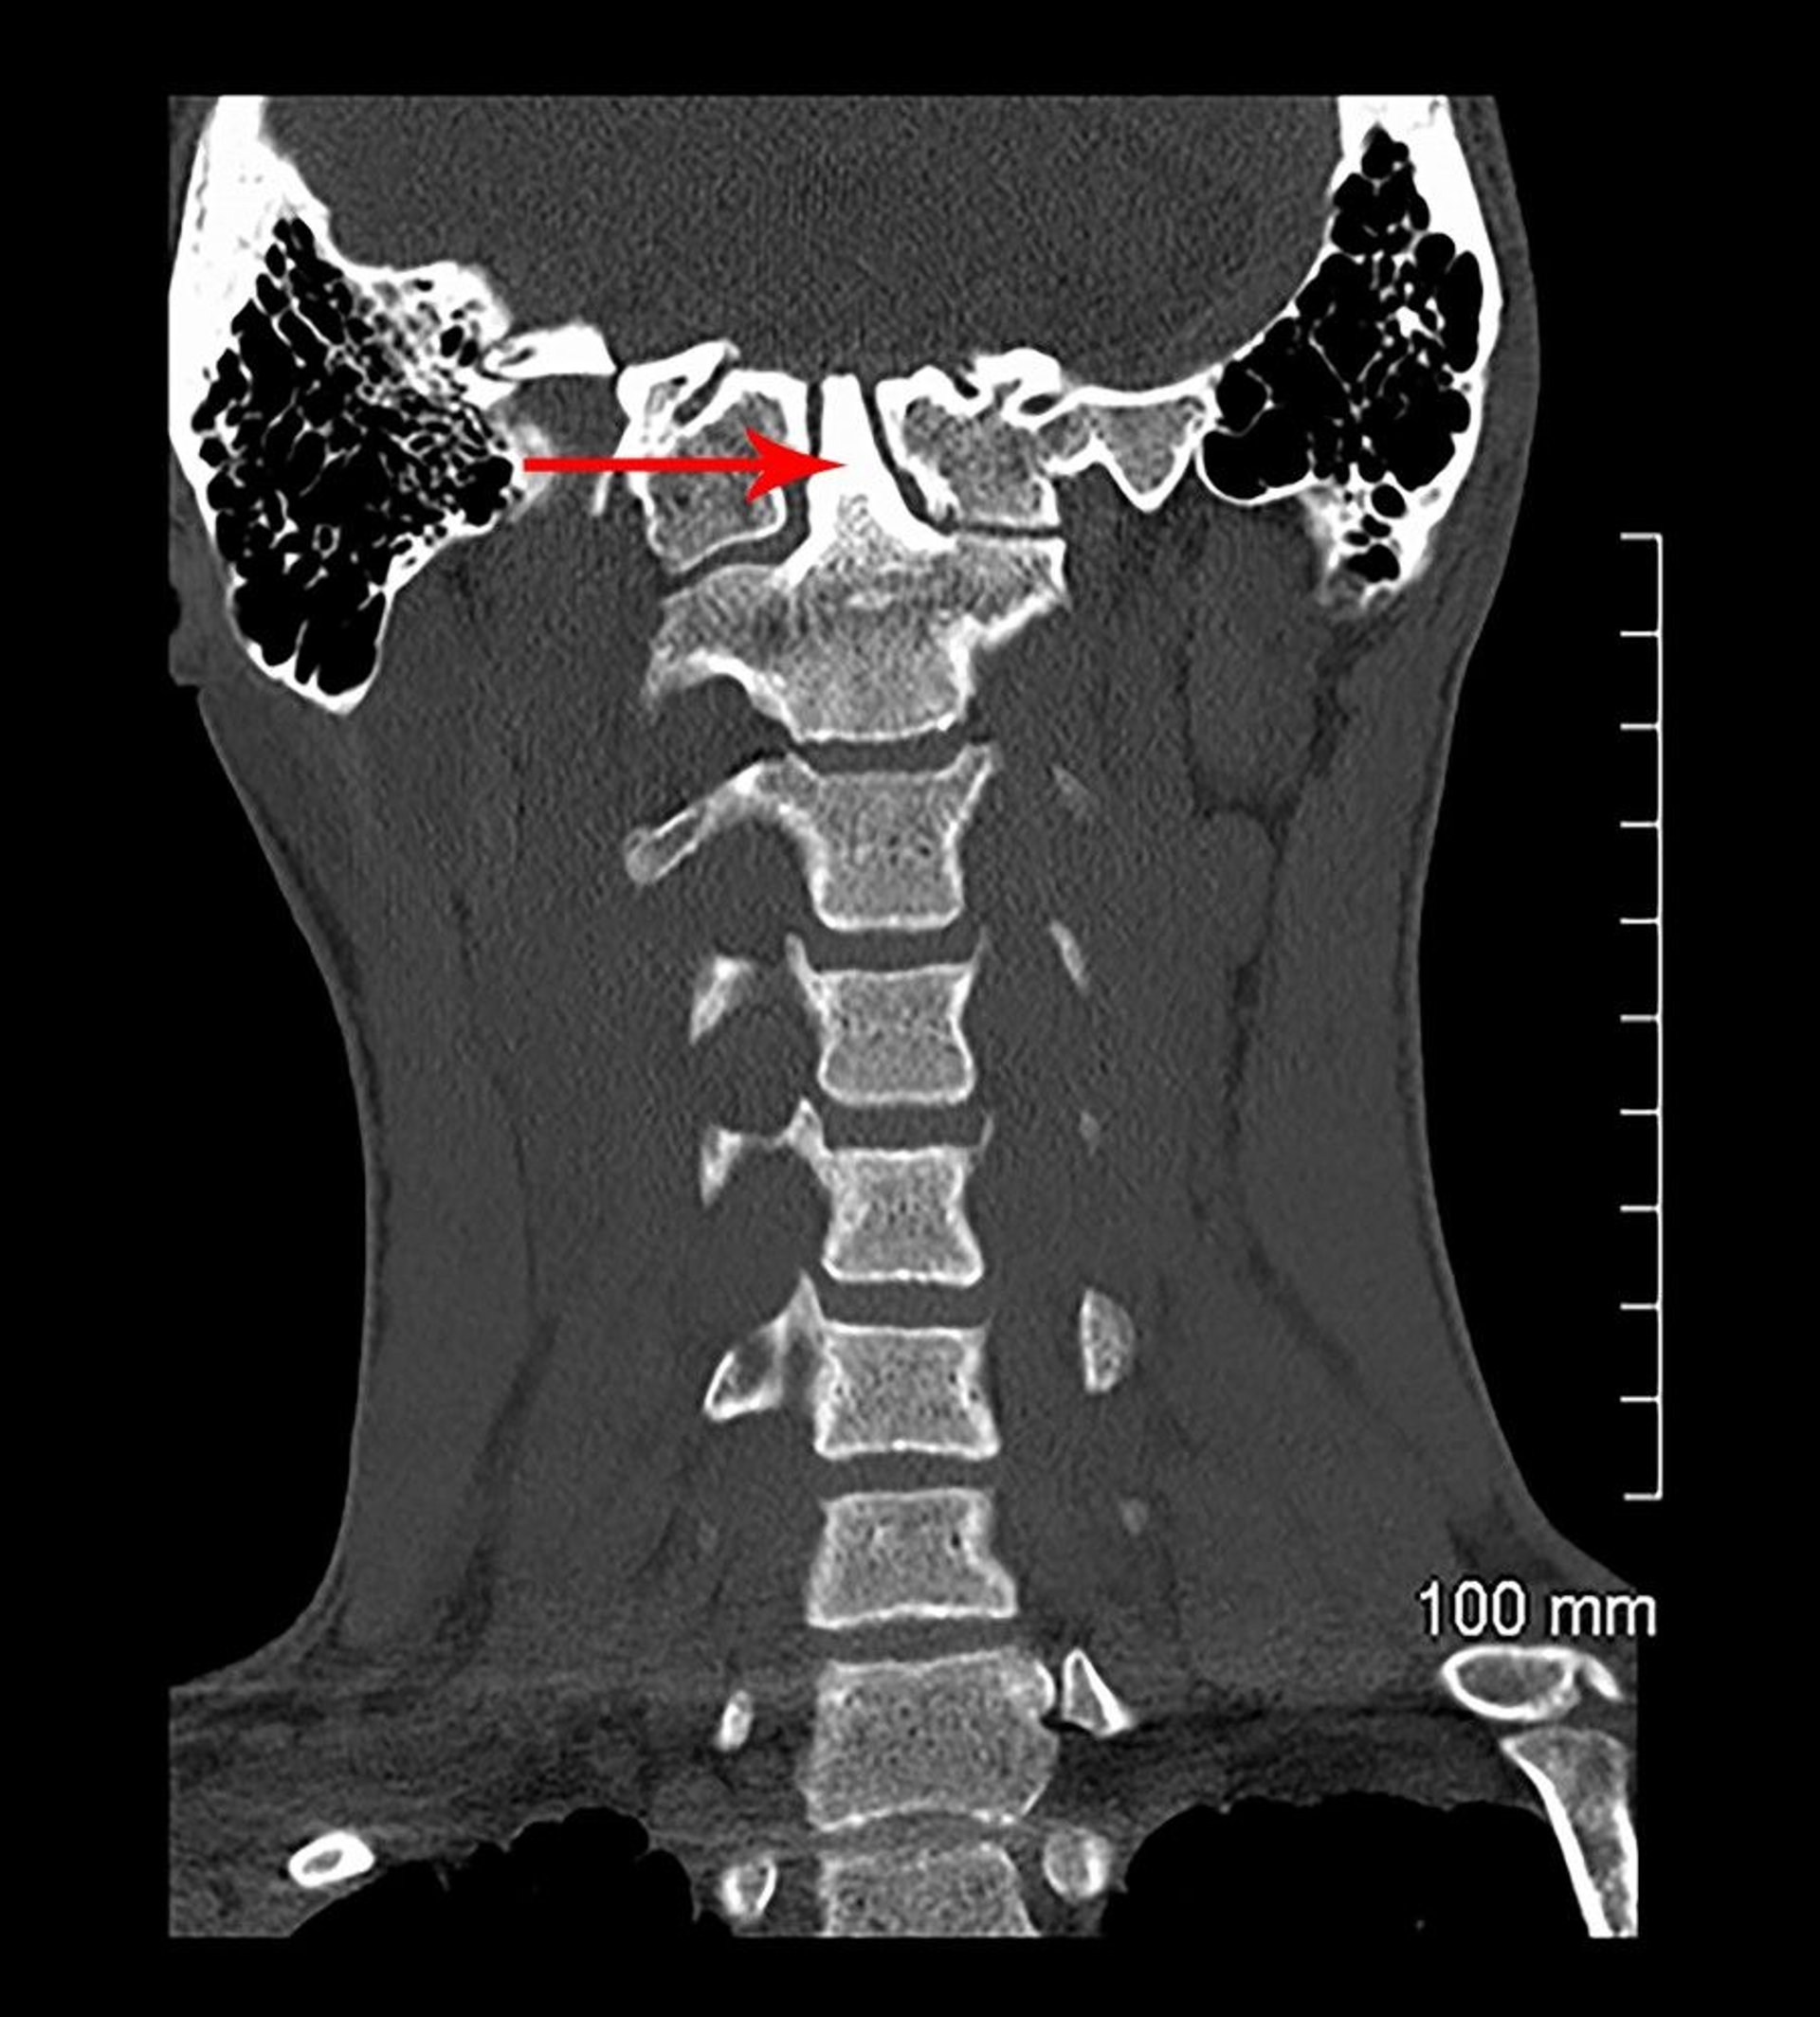

Basilar Invagination and Congenital Assimilation (CT)

In this coronal view of a CT scan, C1 is fused to the skull base (congenitally). The odontoid process (indicated by arrow) extends into the skull base (basilar invagination).